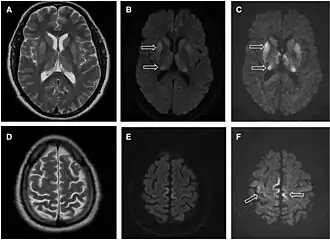

Magnetic resonance image of sporadic CJD[2]

Through the image of MRI, the obvious precipitation of prion protein in the brain is visible.

• MRI with diffusion weighted inversion (DWI) and fluid-attenuated inversion recovery (FLAIR) shows a high signal intensity in certain parts of the cortex (a cortical ribboning appearance), the basal ganglia, and the thalami.[42] The most common presenting patterns are simultaneous involvement of the cortex and striatum (60% of cases), cortical involvement without the striatum (30%), thalamus (21%), cerebellum (8%) and striatum without cortical involvement (7%). In populations with a rapidly progressive dementia (early in the disease process), MRI has a sensitivity of 91% and specificity of 97% for diagnosing CJD.[46] The MRI changes characteristic of CJD may also be seen in the immediate aftermath (hours after the event) of autoimmune encephalitis or focal seizures.[42]

Imaging of the brain may be performed during medical evaluation, both to rule out other causes and to obtain supportive evidence for diagnosis. Imaging findings are variable in their appearance and also variable in sensitivity and specificity.[49] While imaging plays a lesser role in diagnosis of CJD,[50] characteristic findings on brain MRI in some cases may precede onset of clinical manifestations.[51]

Brain MRI is the most useful imaging modality for changes related to CJD. Of the MRI sequences, diffuse-weighted imaging sequences are most sensitive.[52] Characteristic findings are as follows:

• Focal or diffuse diffusion-restriction involving the cerebral cortex or basal ganglia. The most characteristic and striking cortical abnormality has been called "cortical ribboning" or "cortical ribbon sign" due to hyperintensities resembling ribbons appearing in the cortex on MRI.[53] The involvement of the thalamus can be found in sCJD, is even stronger and constant in vCJD.[54]

• Varying degree of symmetric T2 hyperintense signal changes in the basal ganglia (i.e., caudate and putamen), and to a lesser extent globus pallidus and occipital cortex.[50]